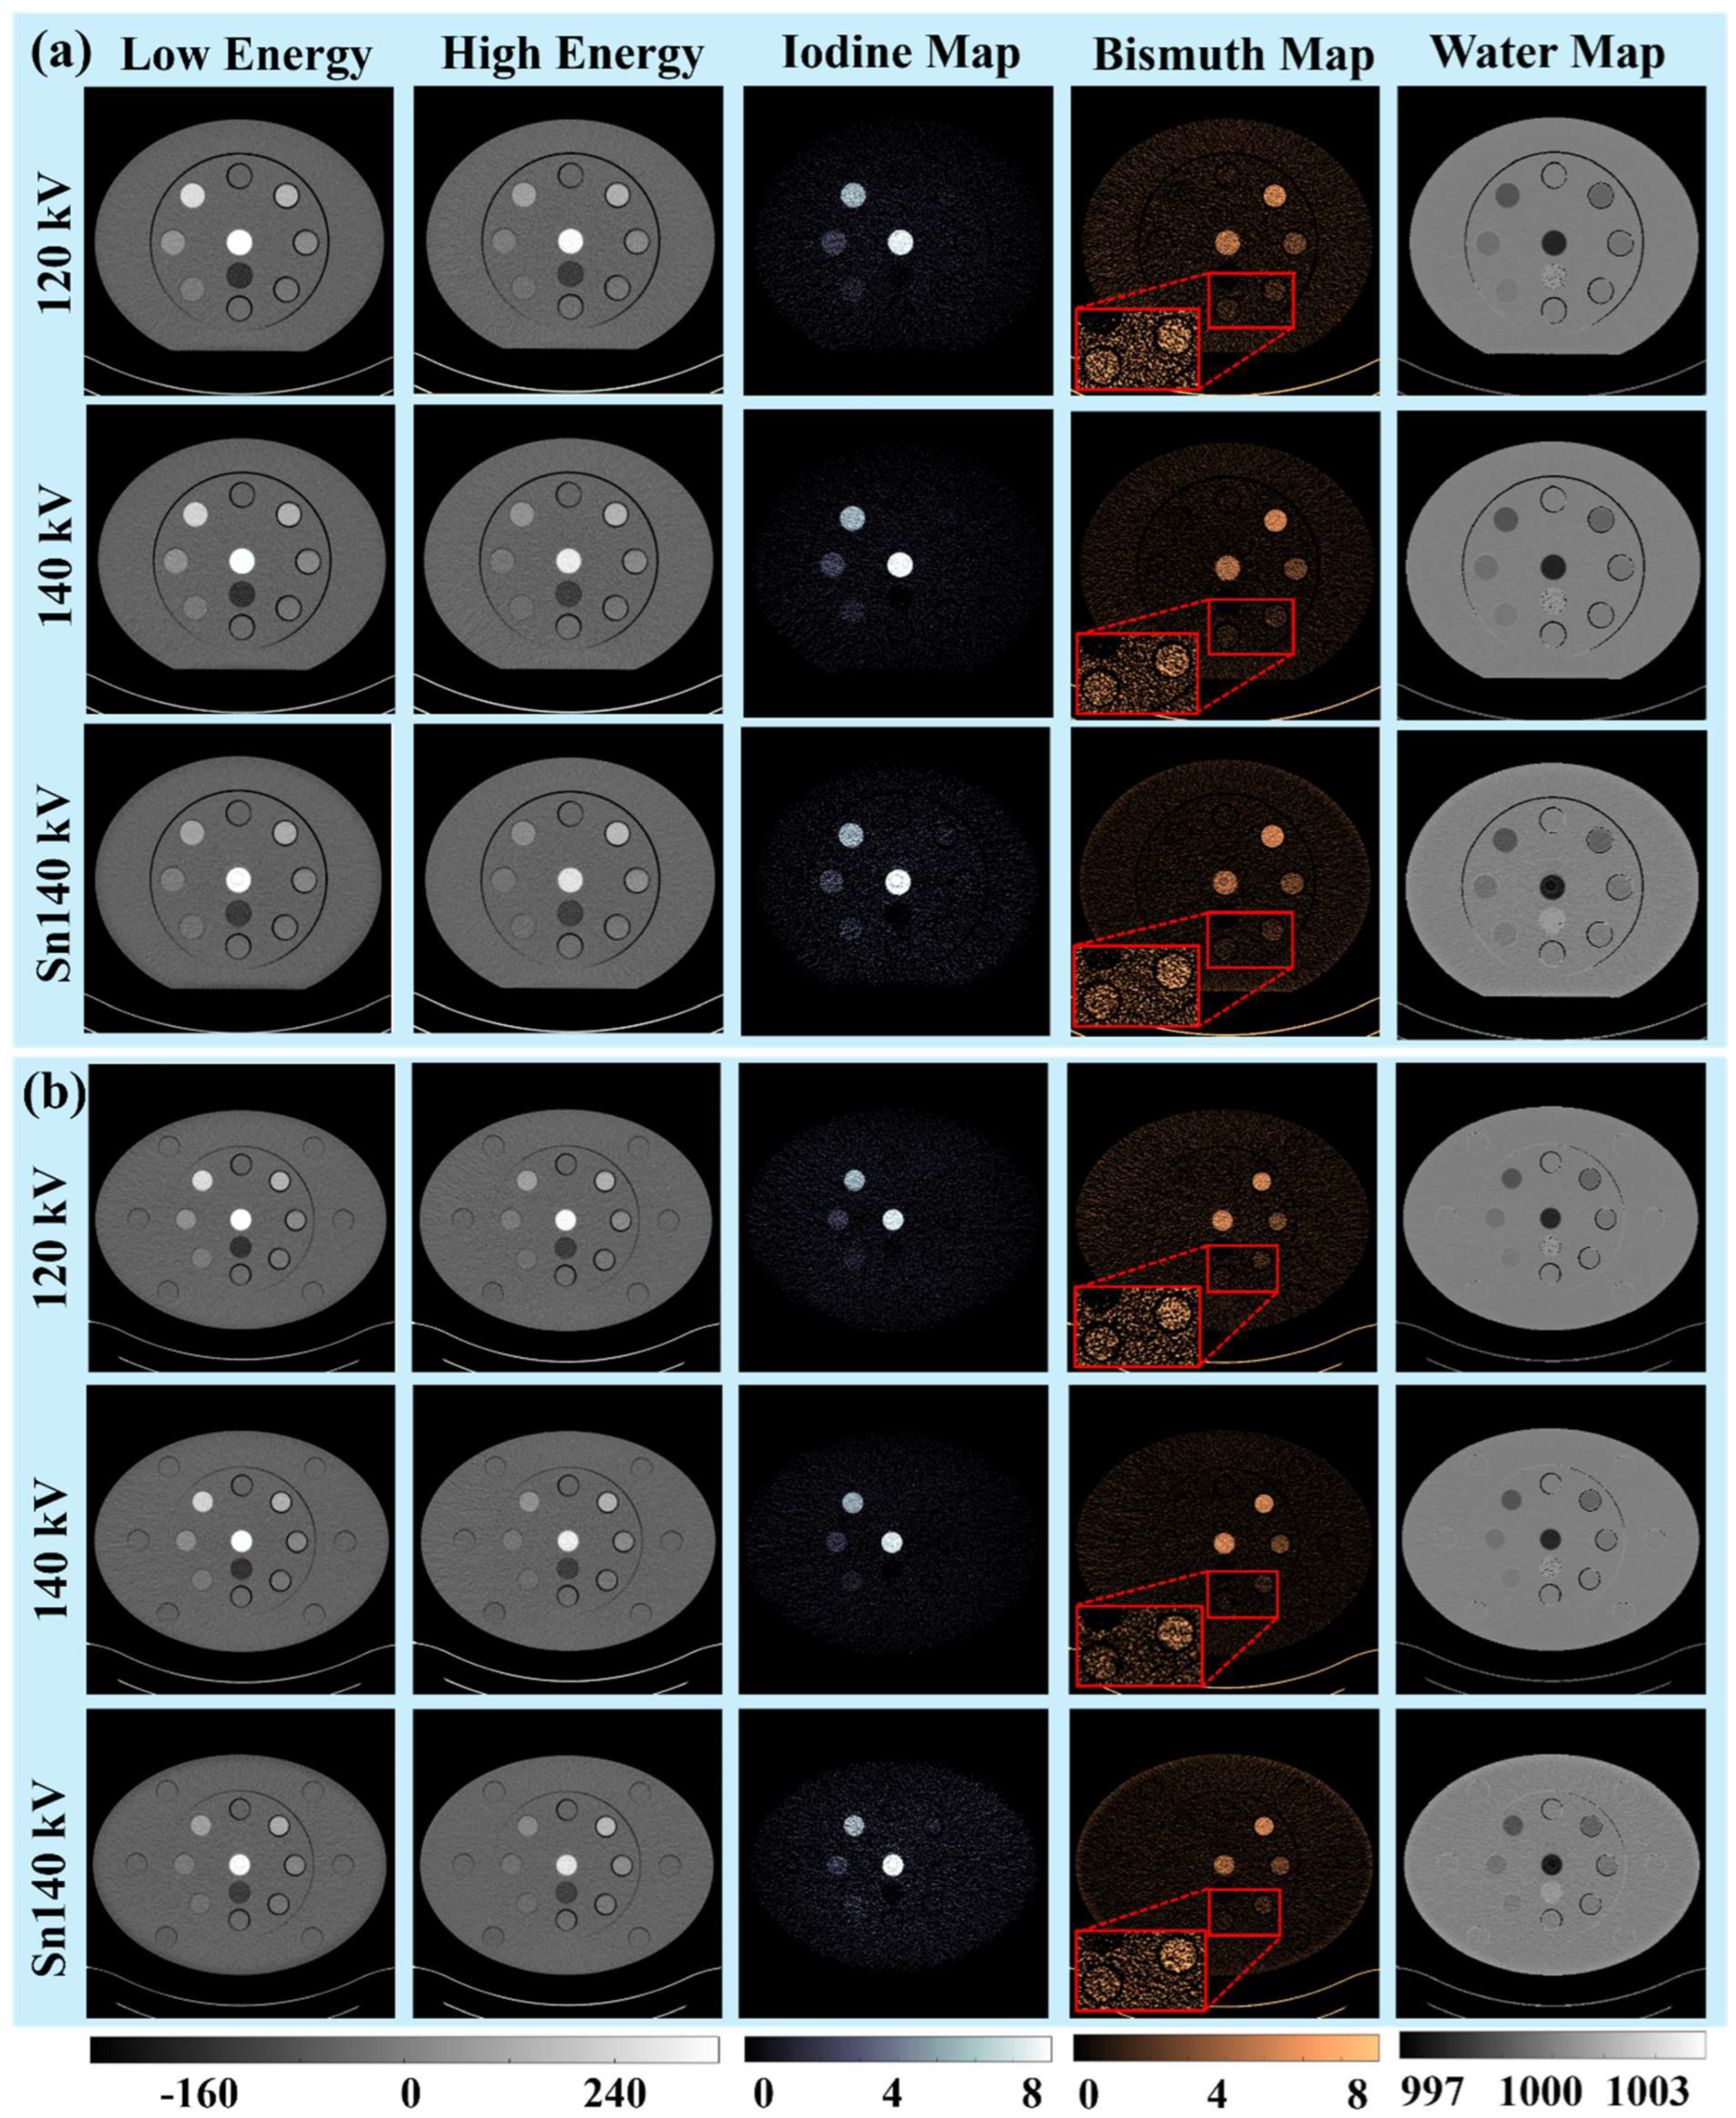

3.1. Visual and Qualitative Evaluations

3.1.1. Iodine and Bismuth Separations

3.1.2. Signals and Noises

3.1.3. Low-Concentration Materials

3.2. Quantitative Evaluations